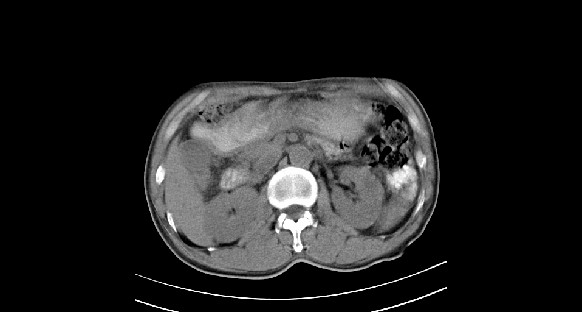

男性,70岁,体检b超发现左肾占位,请各位战友发表一下观点

左肾有两个病灶,且较大的病灶内可见点状钙化灶,增强扫描边缘也是呈渐进性强化,中央部分未见明显强化